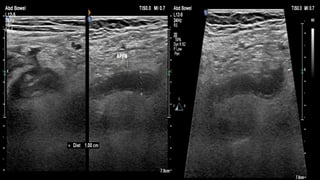

This document discusses the evaluation of right lower abdominal pain and lists appendicitis as a key cause. It notes that other potential causes include hemorrhagic cysts, heterotrophic pregnancy, salpingitis with pyosalpinx, funiculitis, and torsion of an undescended testis. The document was presented by Dr. A.S.M. Sufian of Cumilla Medical College Hospital and thanks the audience for their patience and listening.